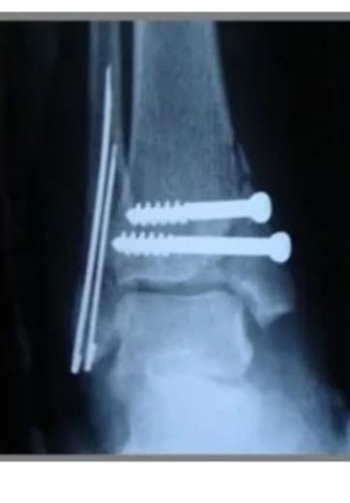

ОСТЕОСИНТЕЗ - это хирургический метод лечения переломов костей, при котором костные отломки фиксируются друг с другом при помощи специальных металлических конструкций (спицы, винты, штифты, гвозди).

Вид металлоконструкции и способ её установки подбираются врачом травматологом-ортопедом индивидуально.

Травматологи-ортопеды клиники №1 ВиТерра Беляево работают с металлоконструкциями (винты\спицы).